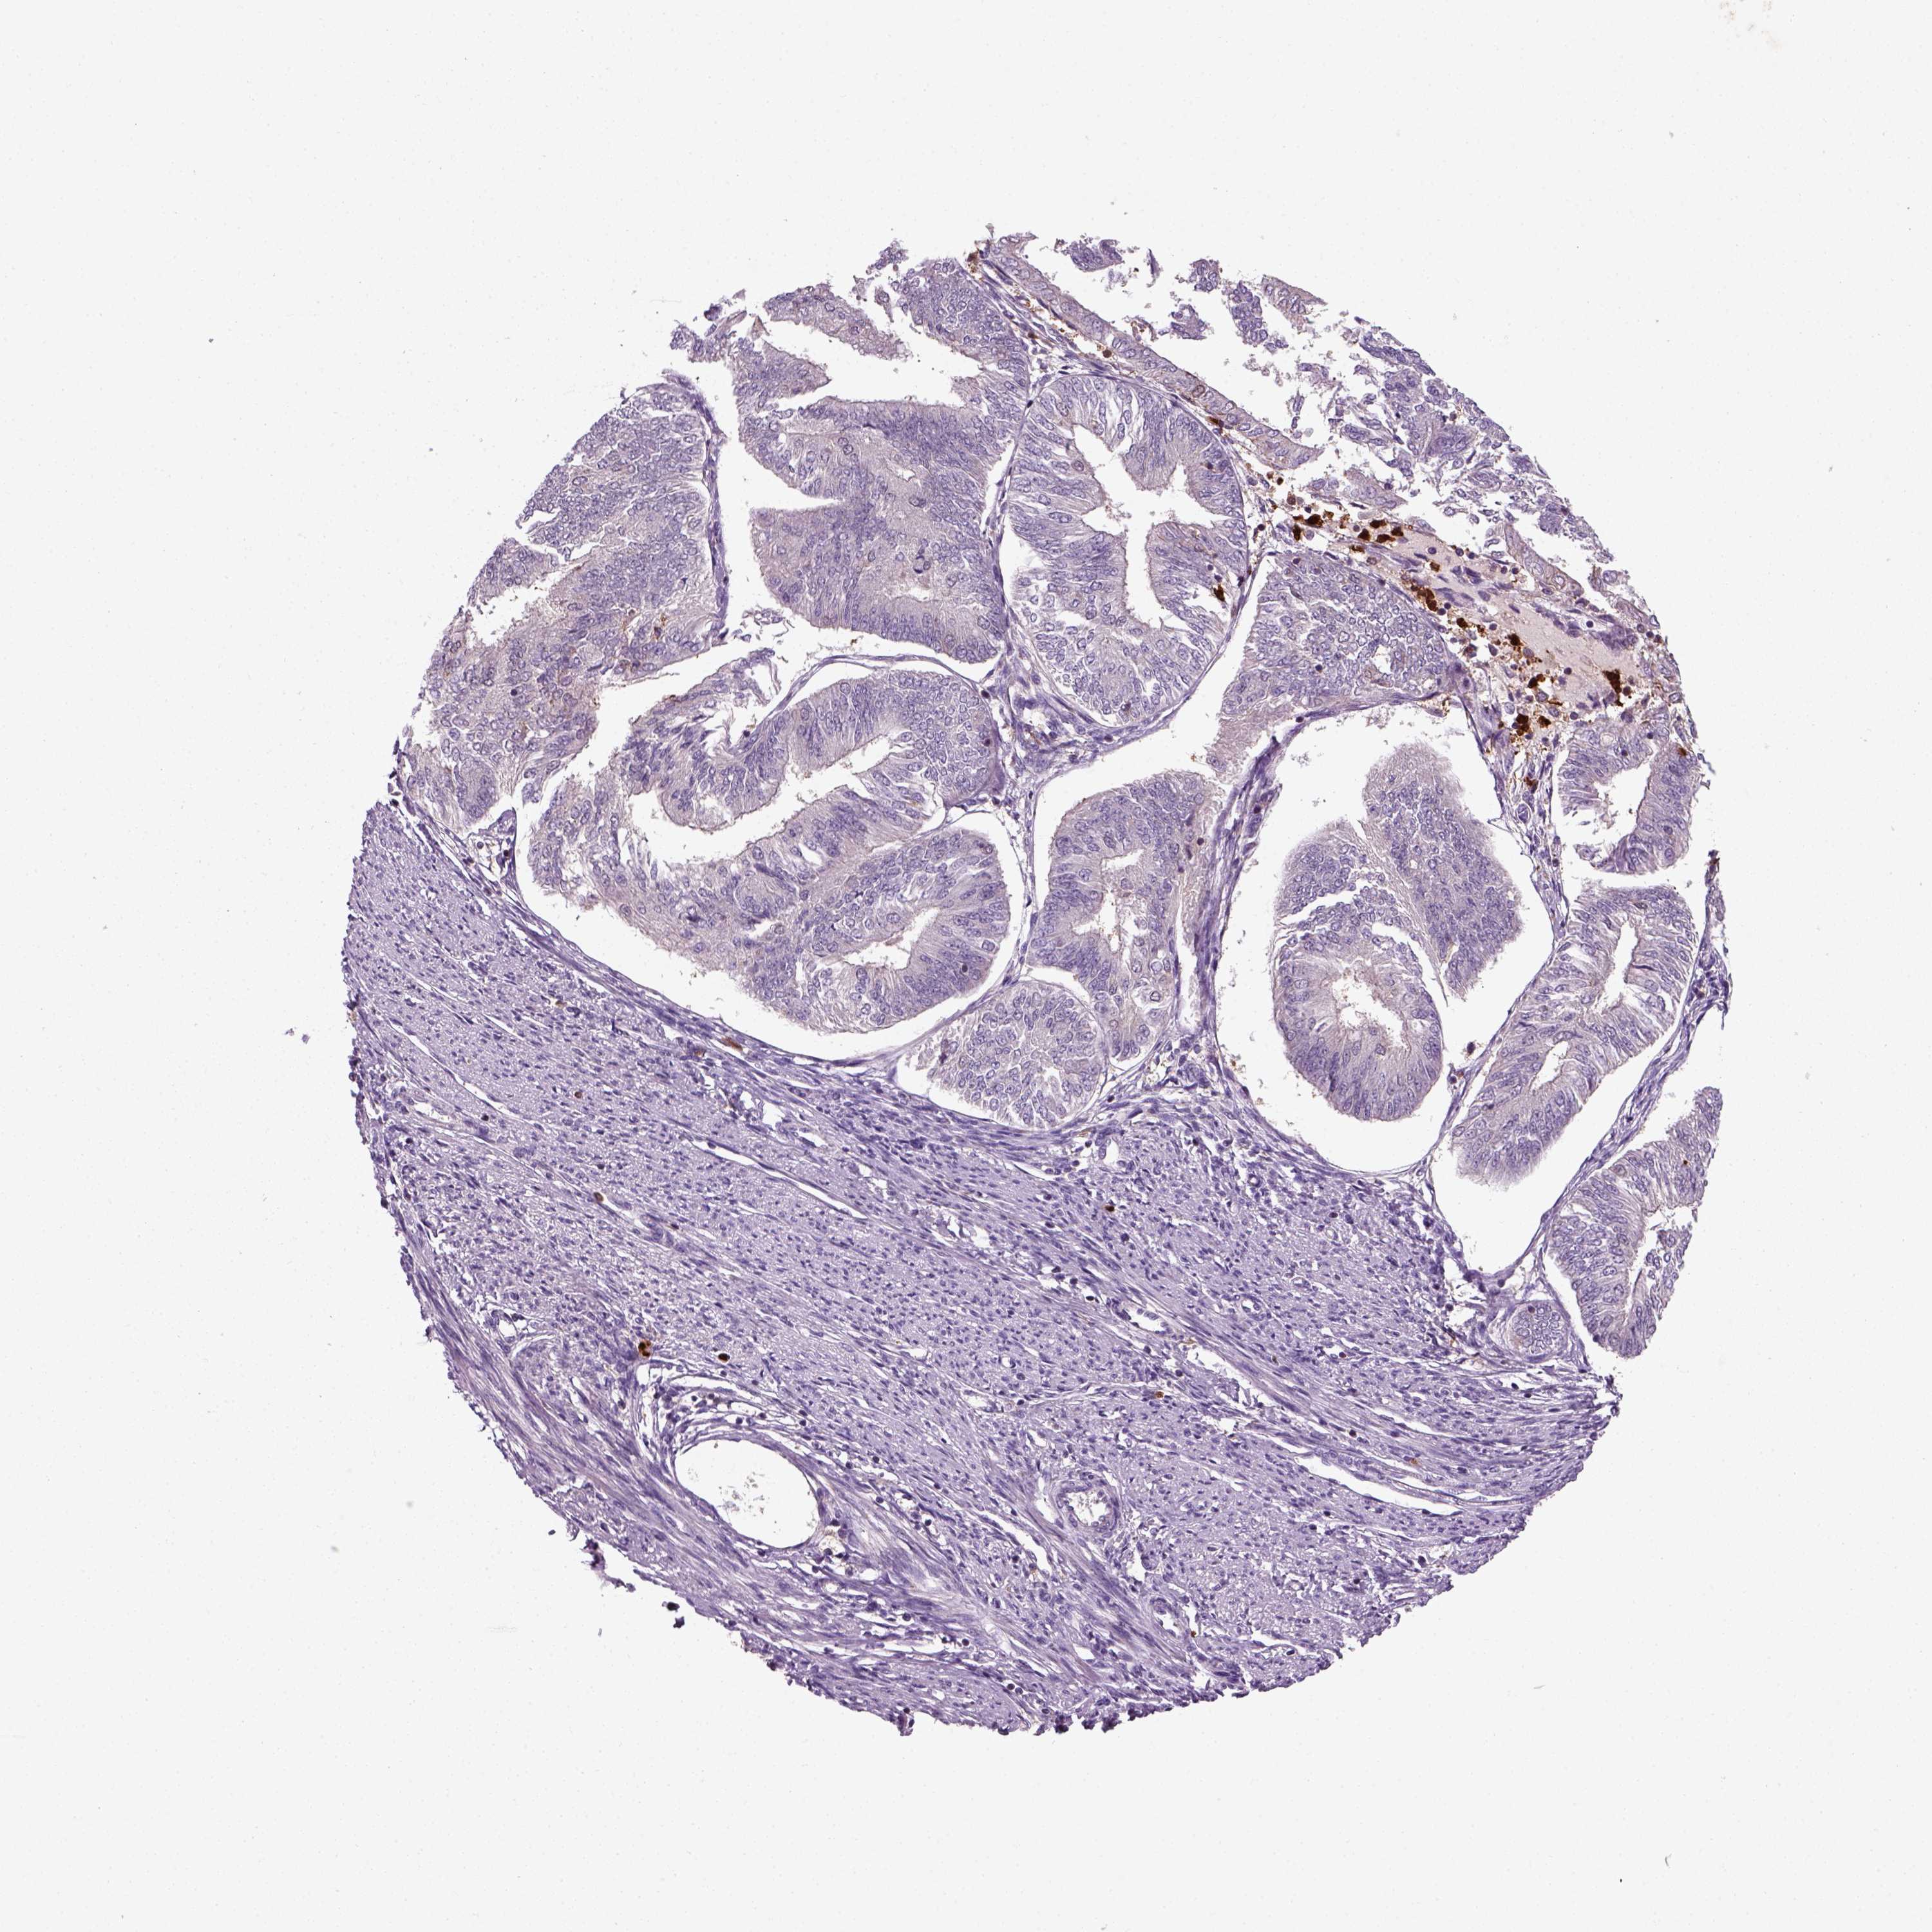

ENDOMETRIAL CANCER - Protein expressioni

A mouse-over function shows sample information and annotation data. Click on an image to view it in a full screen mode. Samples can be filtered based on level of antibody staining by selecting one or several of the following categories: high, medium, low and not detected. The assay and annotation is described here.

Note that samples used for immunohistochemistry by the Human Protein Atlas do not correspond to samples in the TCGA dataset.

Antibody stainingi

Antibody staining in the annotated cell types in the current human tissue is reported as not detected, low, medium, or high, based on conventional immunohistochemistry profiling in selected tissues. This score is based on the combination of the staining intensity and fraction of stained cells.

Each image is clickable and will lead to virtual microscopy that enables deeper exploration of all samples and also displays staining intensity scores, fraction scores and subcellular localization as well as patient and tissue information for each sample.

Antibody HPA044186

Antibody HPA063605

Staining

High

Medium

Low

Not detected

Intensity

Strong

Moderate

Weak

Negative

Quantity

>75%

75%-25%

<25%

None

Location

Nuclear

Cytoplasmic/membranous

Cytoplasmic/membranous,nuclear

Adenocarcinoma, NOS